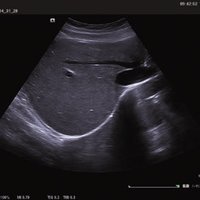

Das ACUSON NX2 Ultraschallsystem besitzt eine zukunftsfähige digitale Plattform mit nahezu unerreichter Bildqualität und sorgt für effiziente und zuverlässige Diagnosedaten. Die Vielseitigkeit des Ultraschallsystems wird mit einem großen kompatiblen Portfolio an Schallköpfen gedeckt, und so ist für jeden Anwendungsbereich etwas dabei. Die Bedienkonsole ist intuitiv aufgebaut und optimiert und erlaubt bis zu vier nach vorne gerichteten Schallkopfanschlüssen für eine enorme Effizienz und schnellen Workflow. So lassen sich bei der fetalen Bildgebung außergewöhnlich detailgetreue Darstellungen des Fetus im Gesicht zeigen oder durch die herausragende Farbdopplersensitivität bei der Darstellung der kleinen Gefäße des zystischen Schilddrüsenknotens kleinste Details erkennen. Weiterhin besticht das NX2 mit einfacher Aufrüstbarkeit bei wachsenden Anforderungen für Ihre zukünftigen Anwendungen und kompatible skalierbare Schallköpfe verringern ihren Kapitaleinsatz um bis zu 31 %.